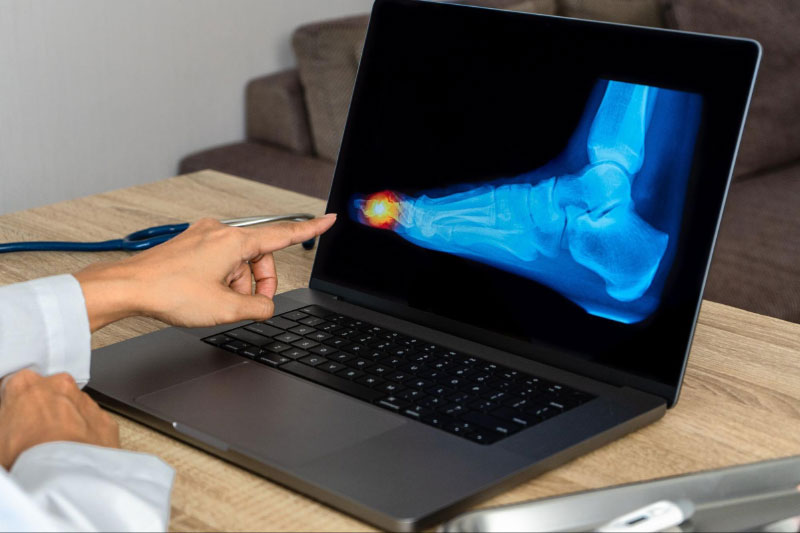

Nếu phát hiện các triệu chứng đau nhức, cứng khớp ngón chân cái hoặc bị tai nạn, té ngã, bạn cần đến các cơ sở y tế để được thăm khăm. Một số phương pháp chẩn đoán có thể được áp dụng để xác định bệnh viêm khớp ngón chân cái là: